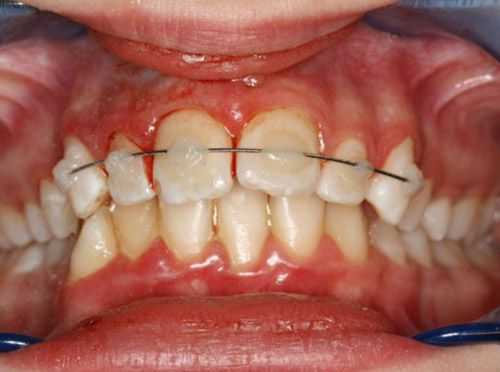

(Слева) На фотографии определяется вколачивание центрального и бокового резцов верхней челюсти справа. Обратите внимание на кровотечение из трещины в десне - признак острой травмы.

(Справа) На периапикальной рентгенограмме у этого же пациента определяется перелом резцового края. (Слева) На фотографии у этого же пациента определяется постепенное самопроизвольное выдвижение зуба и заживление периодонта.

(Справа) На периапикальной рентгенограмме у этого же пациента определяется рарефицирующий остеит возле вершины корня центрального резца верхней челюсти. Рекомендуется лечение корневою канала. Обратите внимание, что гибель пульпы произошла до закрытия вершины корня зуба; вершина корня открыта. (Слева) На фотографии у этого же пациента определяется полное спонтанное выдвижение вколоченною зуба. Сломанные резцовые края могут быть восстановлены композитным материалом.

(Справа) На периапикальной рентгенограмме у этою же пациента - состояние после лечения пульповых каналов с обтурацией их гуттаперчей. Обратите внимание на наружную резорбцию корней обоих резцов.